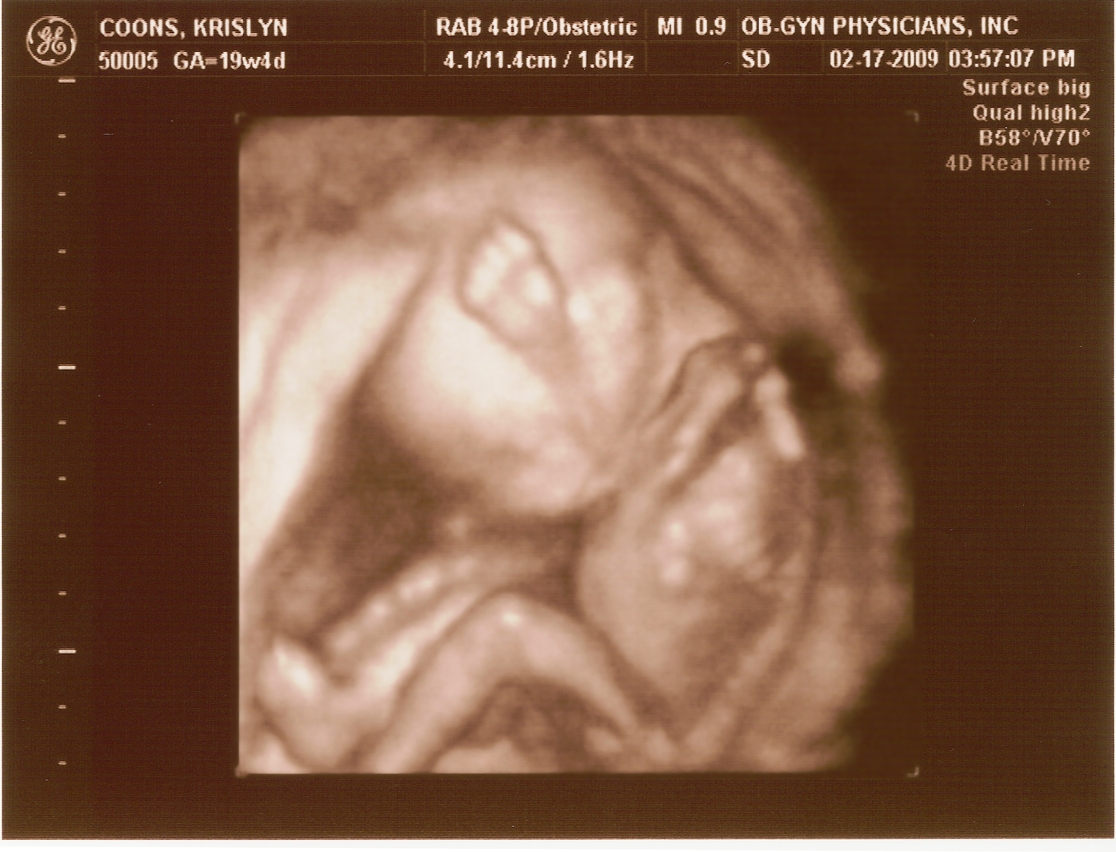

20 weeks

2.17.2009

First ultrasound! The baby measures right on target and appears to be developing normally. All looked and sounded great. Krislyn is finally gaining some baby weight too!